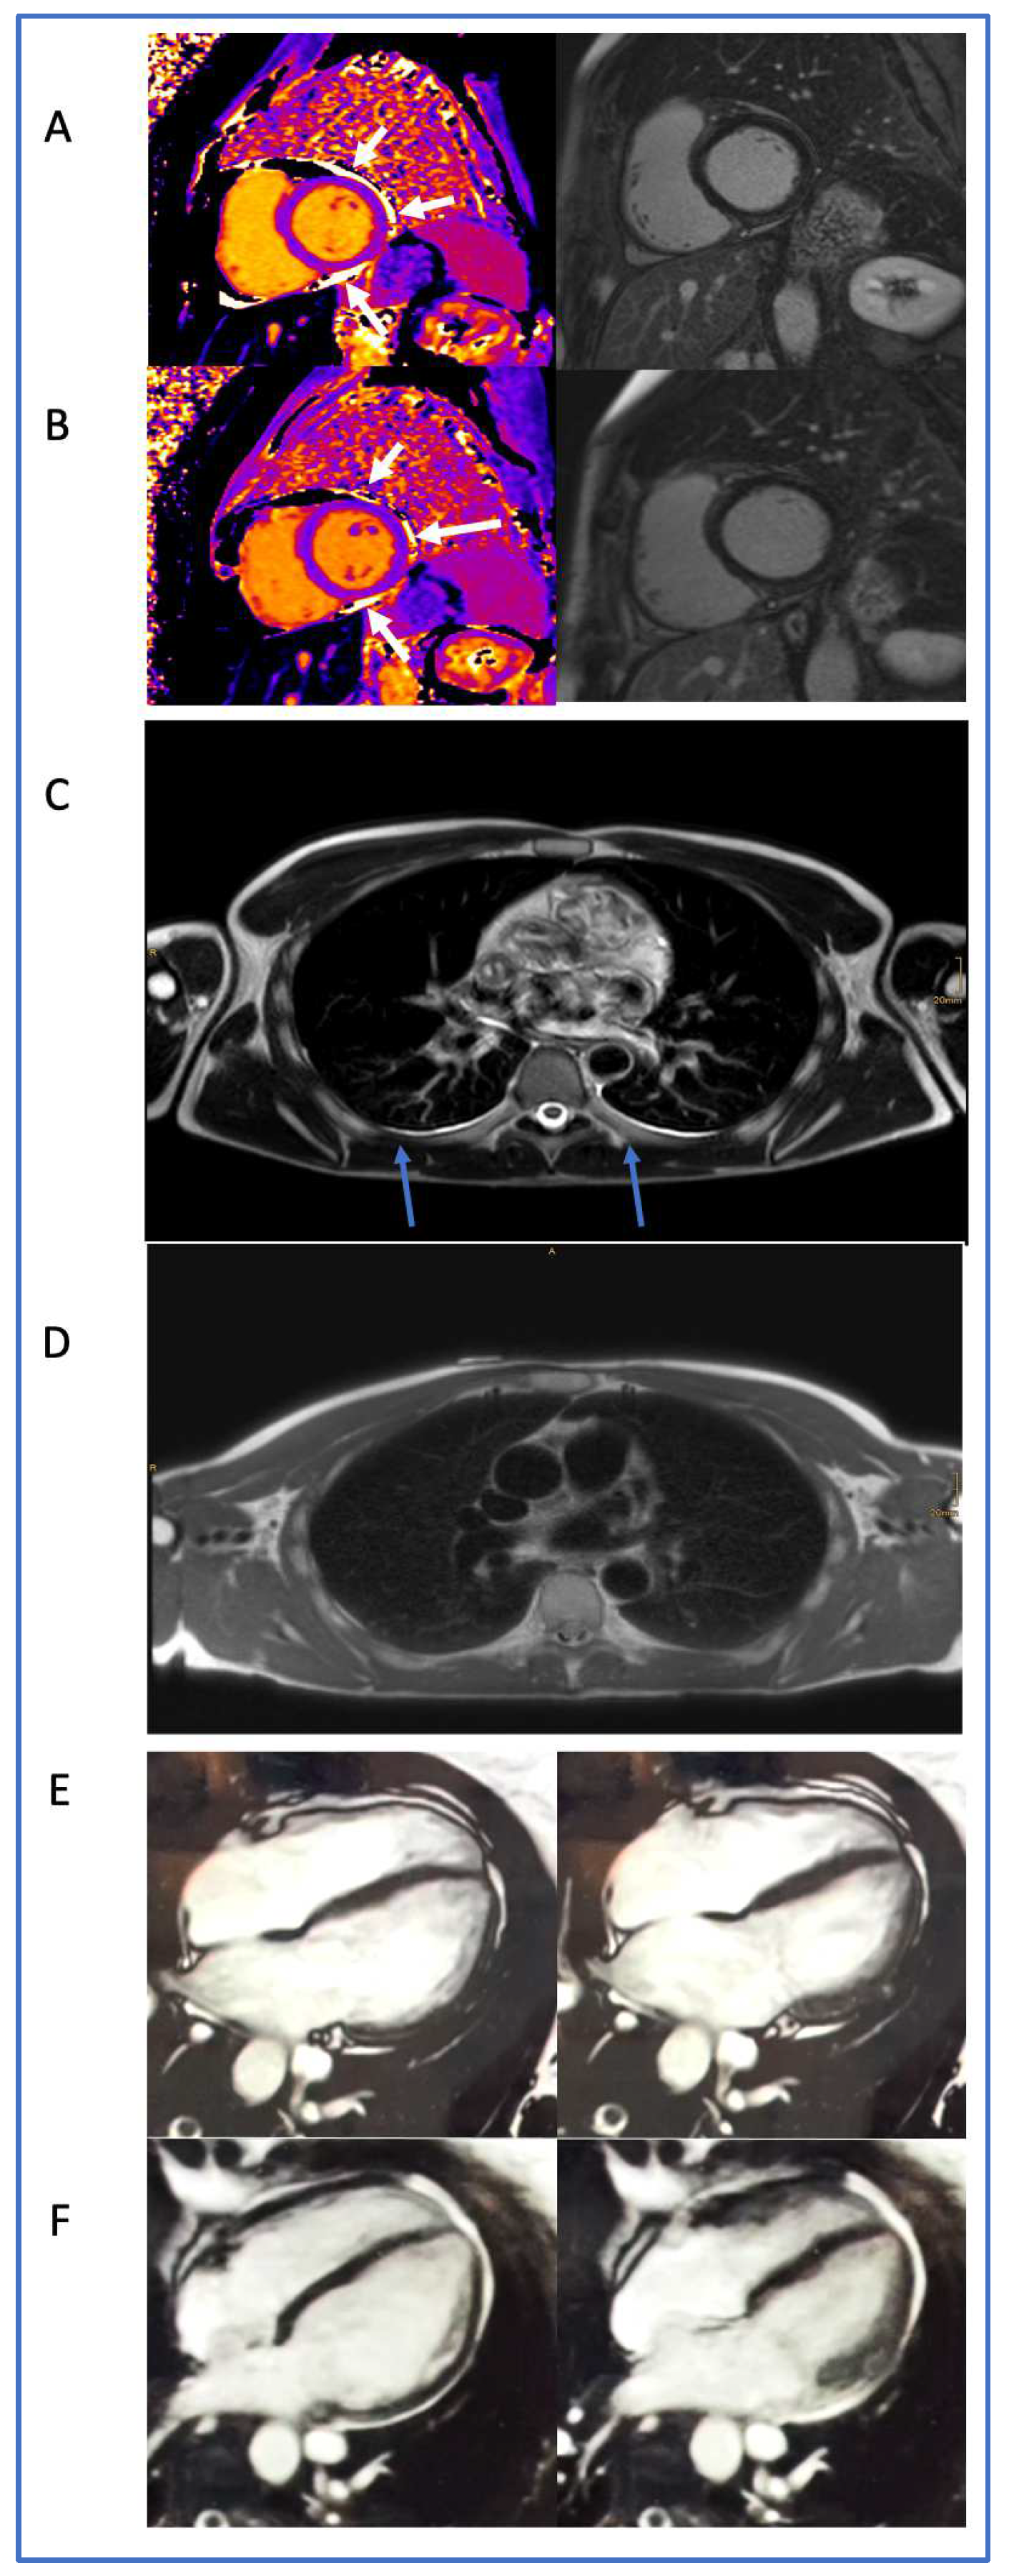

2.5. CMR Acquisition and Analysis